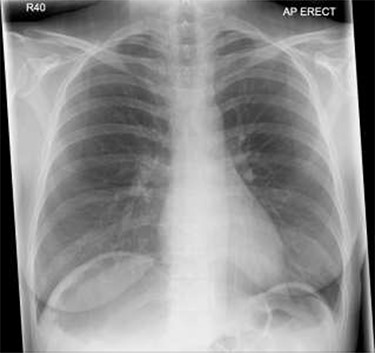

Patient initially diagnosed as biliary colic and surgical team had been contacted. Plain Abdominal radiograph showed dilated small bowels loops (Fig. 1). Chest radiograph revealed air under right hemi-diaphragm (Fig. 2). CT scan was done in emergency department and confirmed interposition of bowel between the diaphragm and the liver with a vascular/mesenteric pedicle swirl suggestive of malrotation or volvulus of the right colon. There was marked mural thickening and bold dilatation with high attenuation mucosa in keeping with closed loop obstruction and possible necrosis (Figs 3 and 4).

CT scan shows a vascular/mesenteric pedicle swirl suggestive of malrotation or volvulus with evidence of dilated closed loop obstruction.